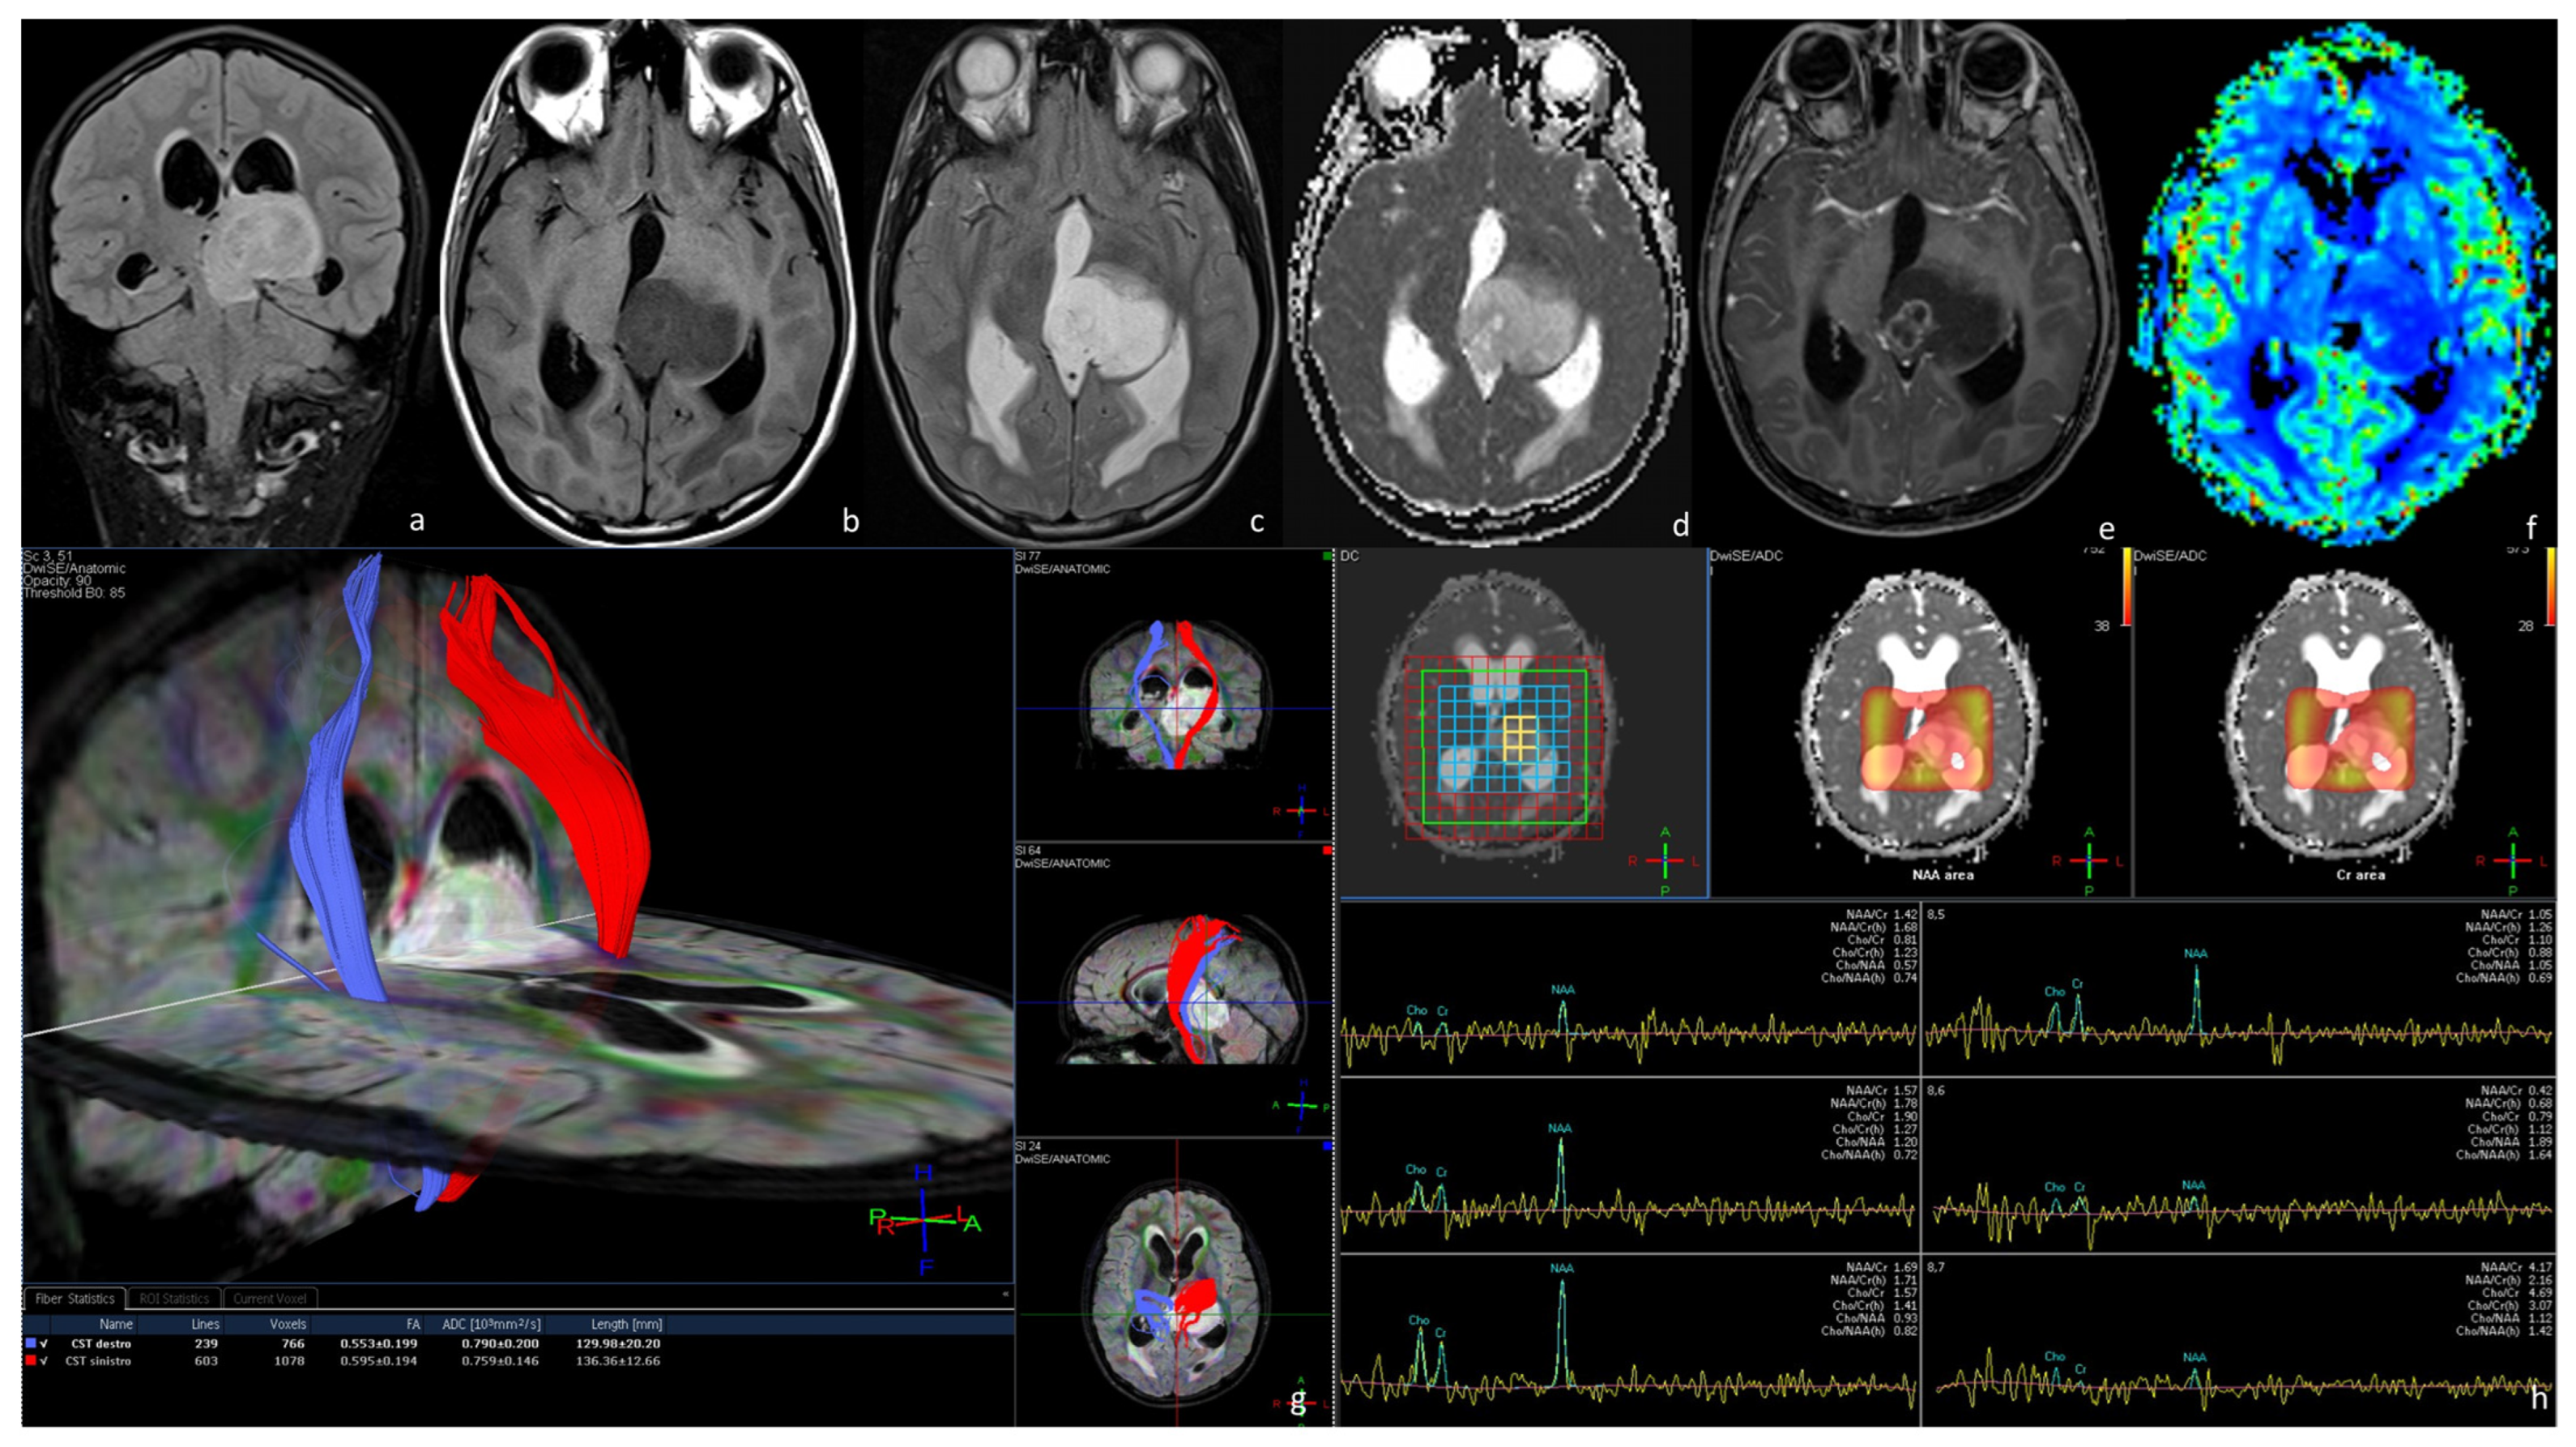

3.1. Diffuse Intrinsic Low-Grade Gliomas (DILGGs)